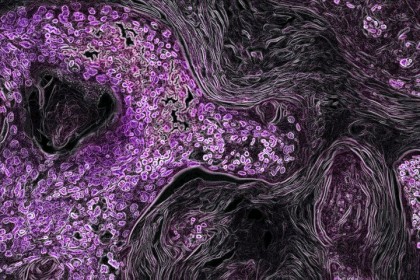

foto: Imagine microscopică a cancerului pulmonar KRAS-pozitiv (violet) într-un model de șoarece. Cercetătorii au descoperit că tumorile KRAS-pozitive au niveluri mai mari de fier feros, ceea ce se coreleaza cu timpi de supravietuire mai scurti. Image by National Cancer Institute, National Institutes of Health

Cercetătorii au descoperit că multe tumori determinate de forma KRAS a mutațiilor RAS au concentrații crescute de fier feros și că acest lucru este corelat cu timpi de supraviețuire mai scurți. Pentru a profita de această caracteristică unică a celulelor canceroase, cercetătorii au sintetizat o nouă versiune a cobimetinibului, căruia i-au atașat un senzor molecular mic de fier feros. Senzorul poate opri în mod efectiv cobimetinibul până când medicamentul întâlnește fierul feros în celulele canceroase.